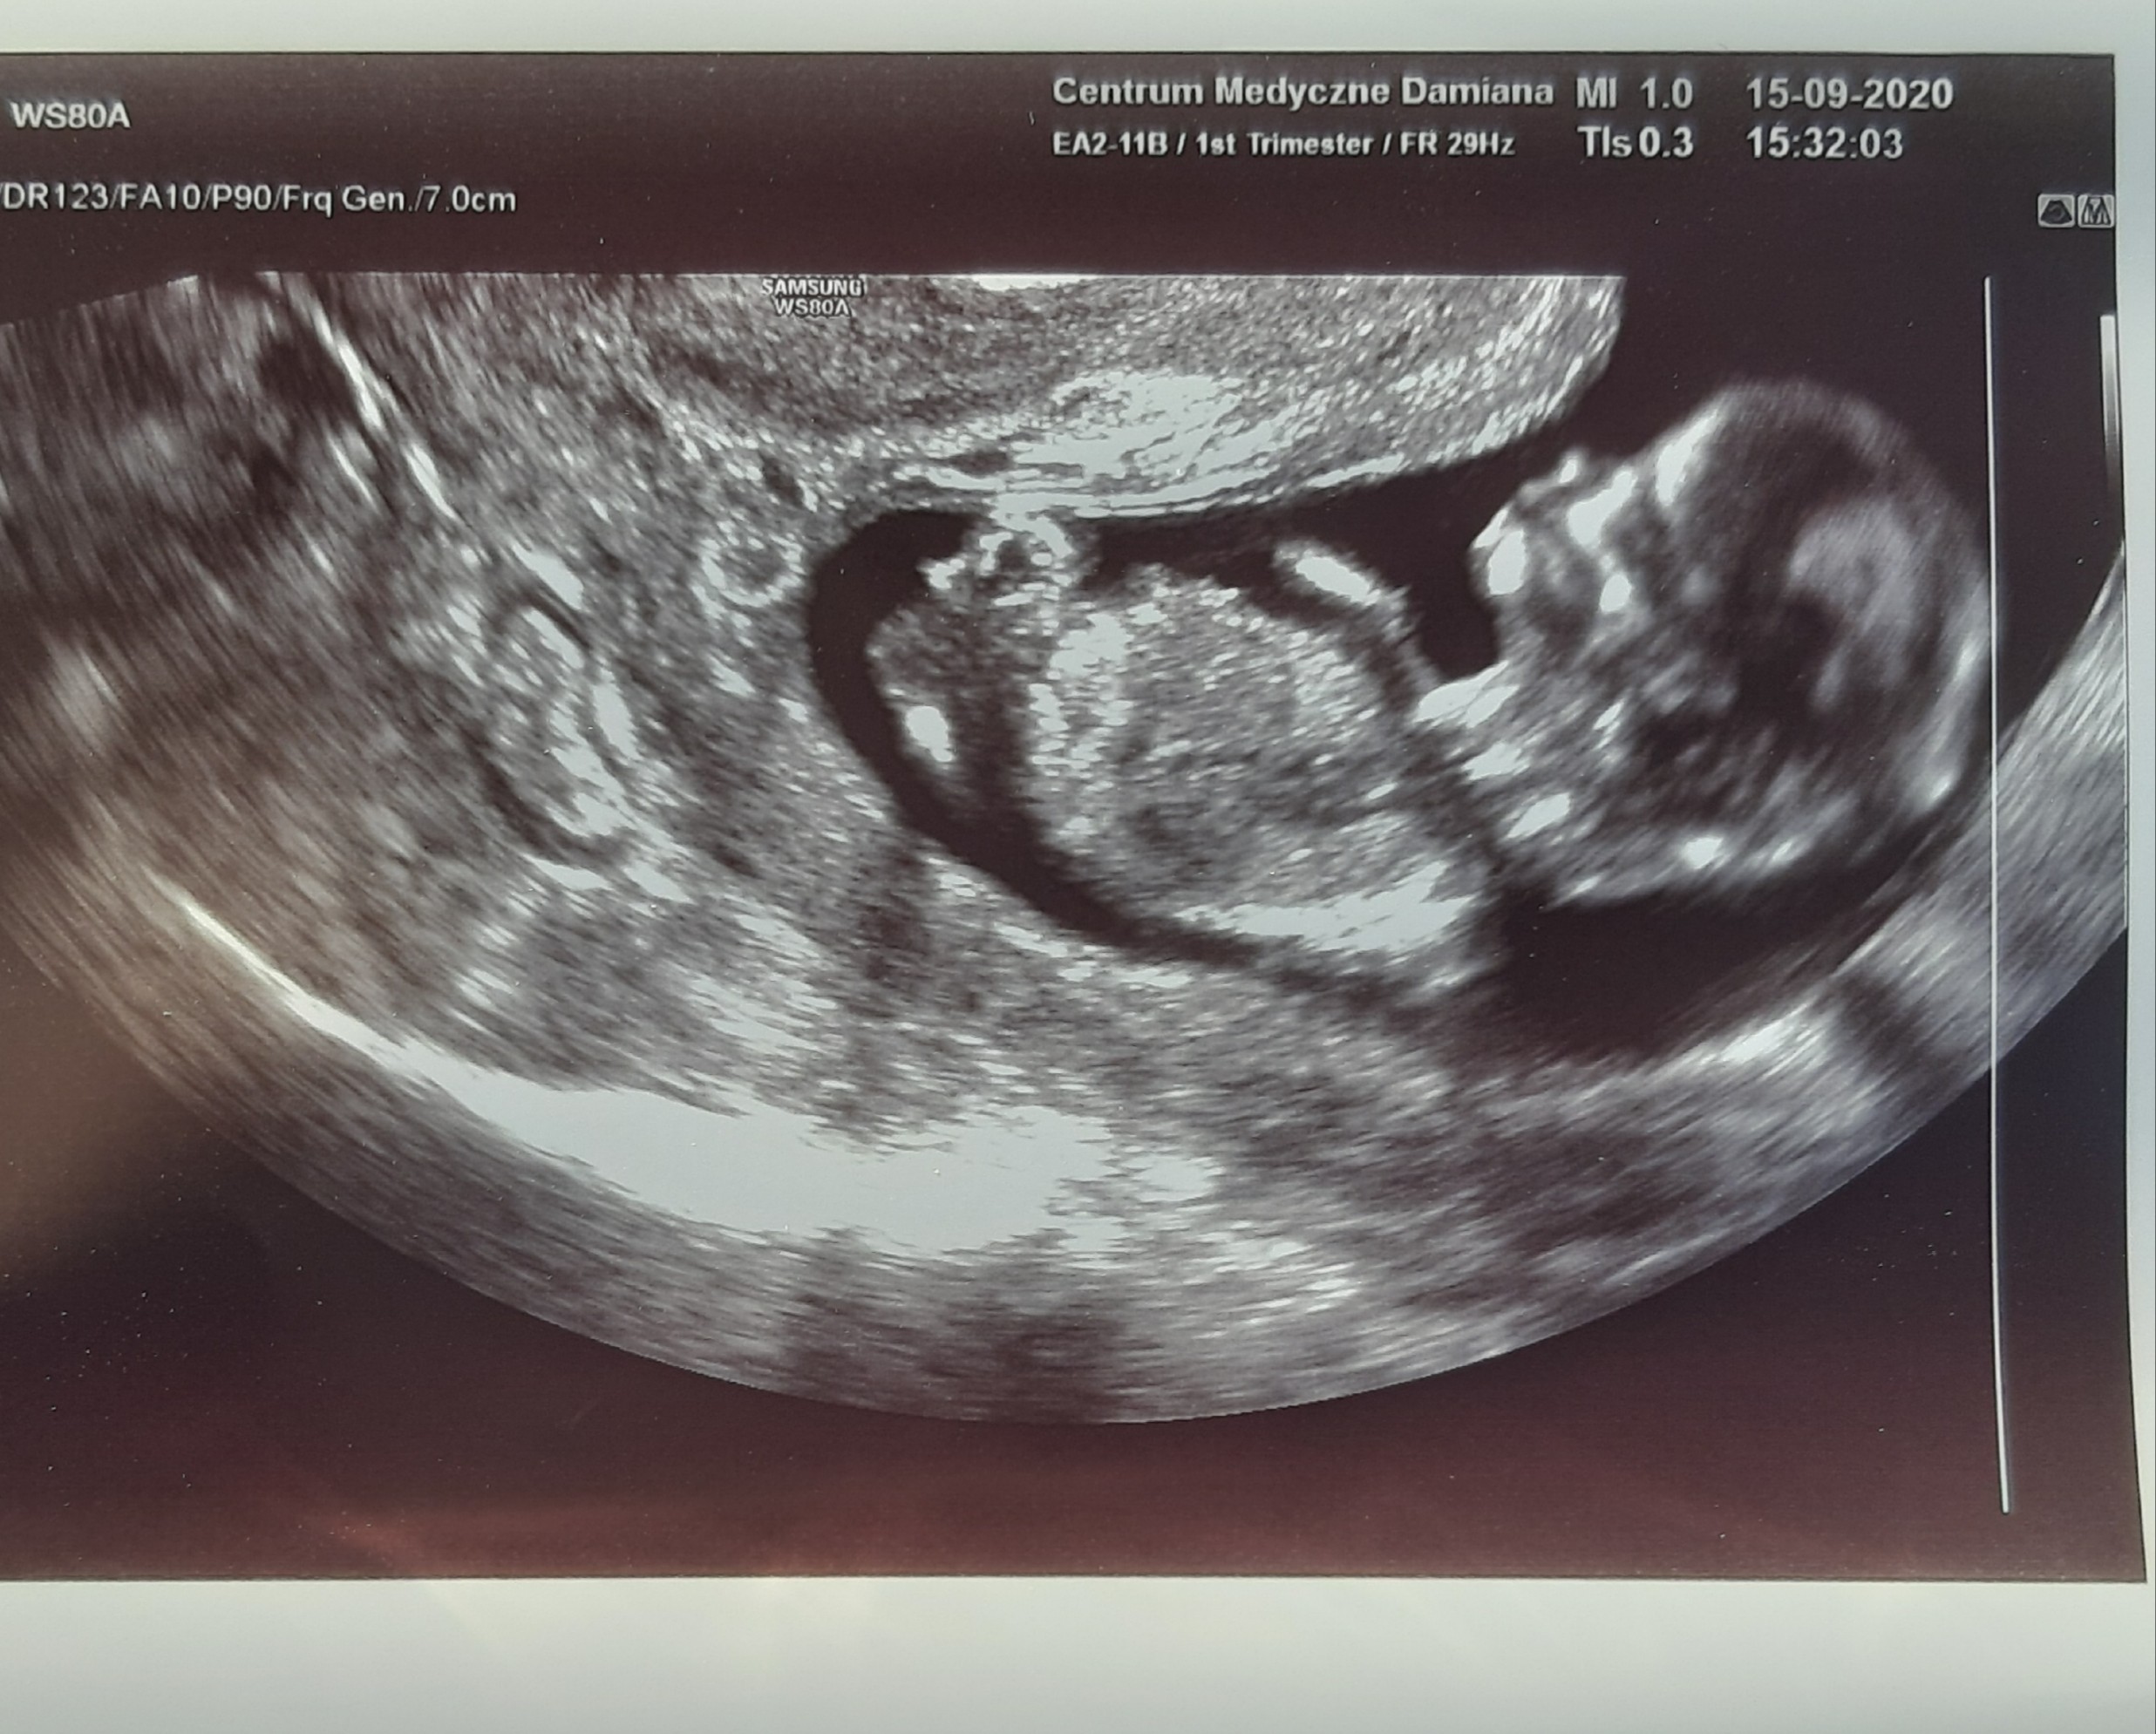

Generalnie już jestem po badaniach - samo usg wyszło bardzo dobrze, wszystko w normie, maluszek ma 8 cm i niezbyt był skłonny do współpracy 😉 ale wszystkie pomiary ok, kość bosowa ok, przezierność 1,9.